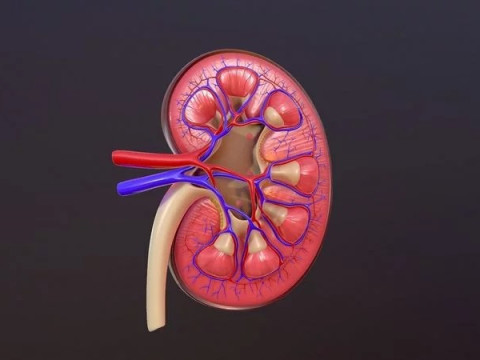

Human Kidney Low-poly Modelo 3D

Human Kidney Modelo 3D blend, jpg, fbx, max, De jack2024

human kidney renal urine organ anatomical health people anatomy biology urinary system electrolytes internal organs science medical crossNo hay comentarios sobre este artículo.